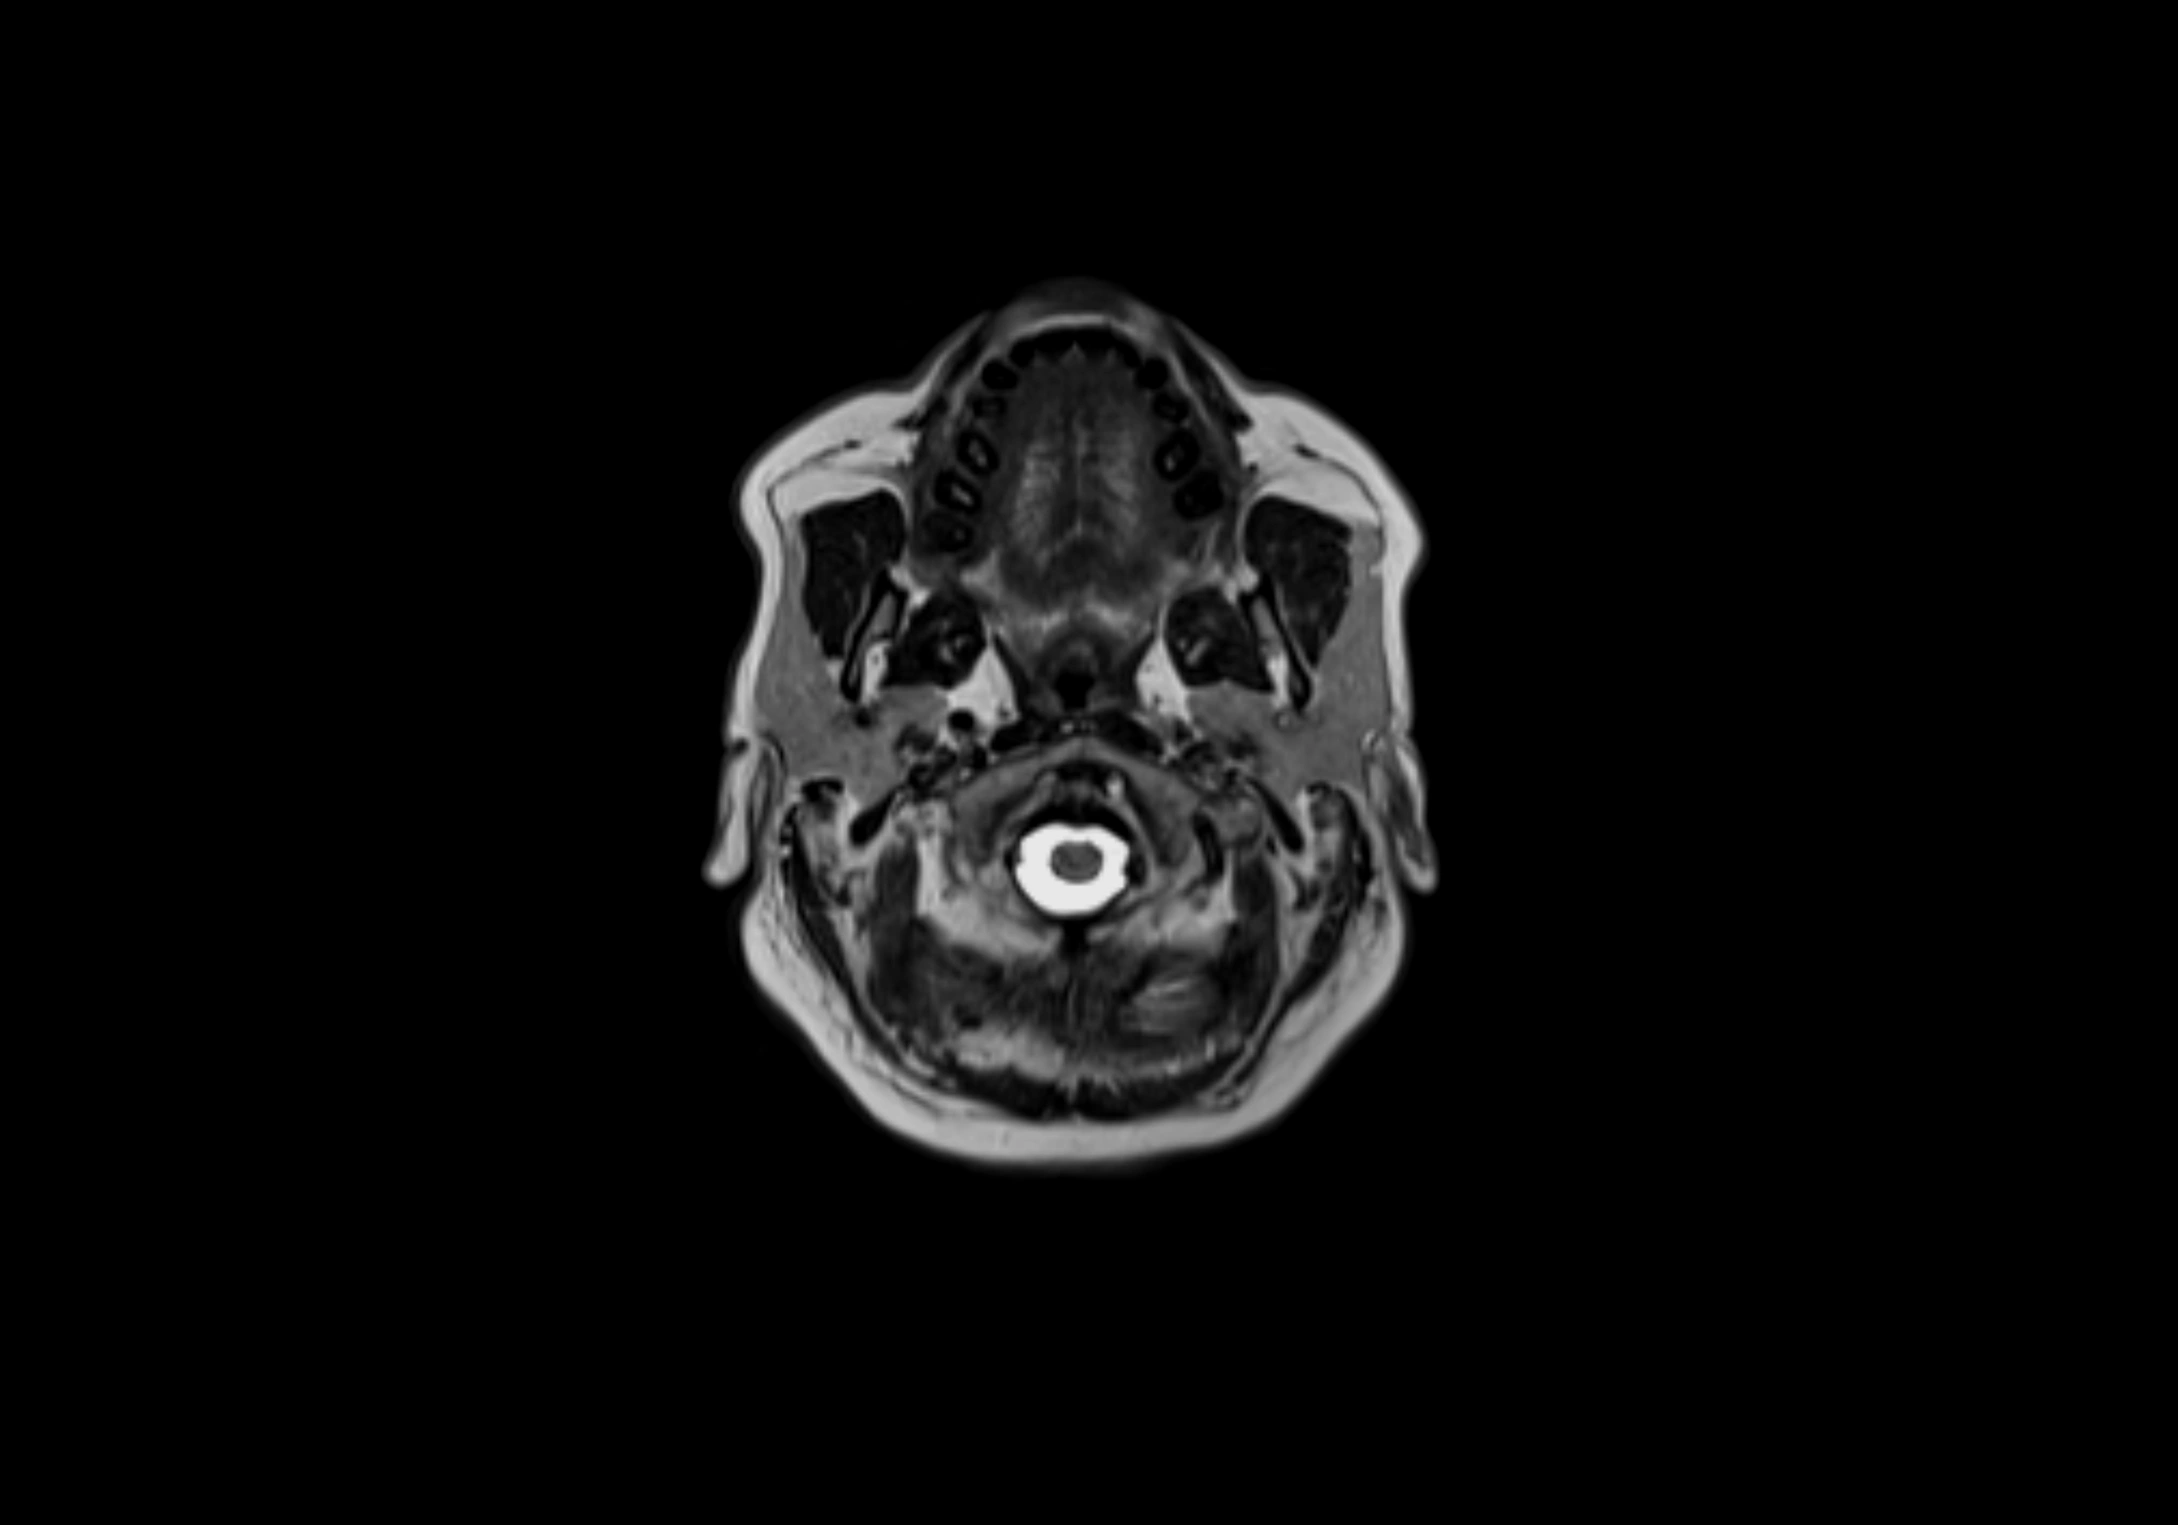

MRI Appearance

T1-weighted images:

• Normal accessory nodes appear as small, oval hypointense to intermediate signal structures within subcutaneous fat

• Surrounded by hyperintense fat, enhancing contrast for visualization

T2-weighted images:

• Nodes show intermediate signal, with surrounding fat bright

• Useful for detecting edema, inflammation, or infiltration